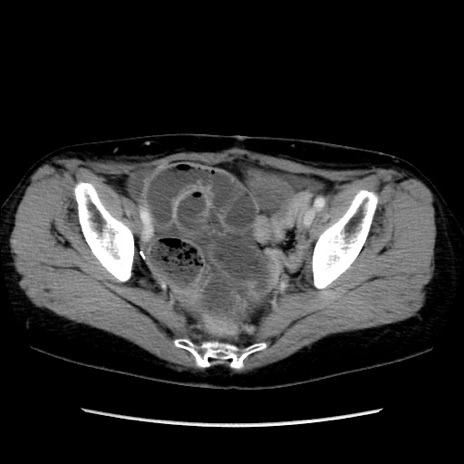

症例32(横断像)

【症例】40歳代 女性

【主訴】上腹部痛、嘔気・嘔吐

【現病歴】約9時間前頃から急に上腹部痛、嘔気、嘔吐が出現。改善しないため救急要請。

【既往歴】子宮頚癌(広汎子宮全摘術、放射線療法)、腸閉塞

【身体所見】腹部:平坦、軟、腸雑音亢進、上腹部を中心に腹部全体に圧痛あり。

【データ】WBC 8400、CRP 0.03